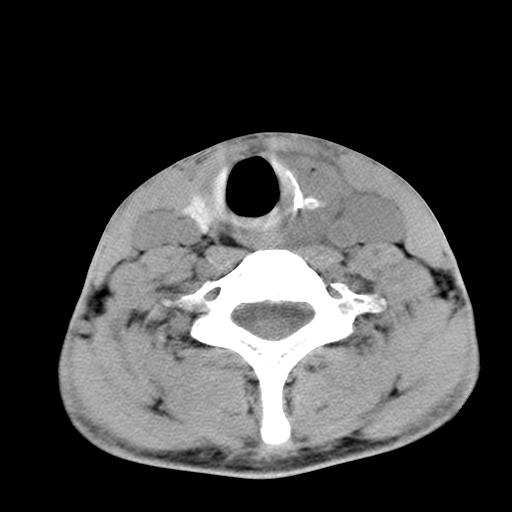

标题: CT15118:f-27y,左颈部肿一个月,无发热、无压痛 [打印本页]

标题: CT15118:f-27y,左颈部肿一个月,无发热、无压痛

1、甲状腺左叶病变:腺瘤?结节性增生?其他?

2、上极周围间隙病变。

3、2者关系?

左侧甲状腺肿大,密度不均.同侧甲状软骨似有破坏(建议传骨窗).左侧颈静脉增粗,各组织之间分界不清,有多个肿大淋巴结.甲状腺肿并感染?临床症状不符.淋巴结核?请结合其他检查.